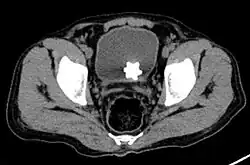

The diagnosis of bladder stone includes urinalysis, ultrasonography, x rays or cystoscopy (inserting a small thin camera into the urethra and viewing the bladder). The intravenous pyelogram can also be used to assess the presence of kidney stones. This test involves injecting a radiocontrast agent which is passed into the urinary system. X-ray images are then obtained every few minutes to determine if there is any obstruction to the contrast as it is excreted into the bladder. Today, intravenous pyelogram has been replaced at many health centers by CT scans. CT scans are more sensitive and can identify very small stones not seen by other tests.[8]

A star-shaped Jackstone urolith can be seen in the urinary bladder on this radiograph of the pelvis